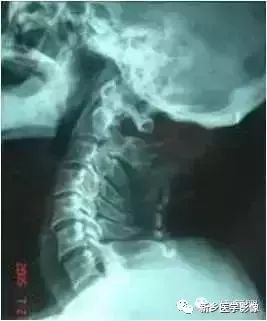

颈椎侧位

颈椎侧位片可以观察椎体前缘连线形成的弧度及生理曲度的变化,在正常情况下稍向前凸。观察椎体的整体形状,对比每个椎体的变化。观察每个椎体与上下椎体之间的关系。寻找椎体后缘可疑的变化。如椎体脱位。观察椎间隙及相邻椎体的边缘。观察有无A 椎间隙变窄;B 前缘唇样变;C 后缘唇样变;D 强直性脊柱炎所致的椎体融合。

①、曲度的改变:颈椎变直、生理前突消失或反弯曲,除病人的投照位置、投照角度等技术因素之外,可能会有几种原因:

第一、颈部软组织发生急性扭伤或纤维织炎,疼痛剧烈或有肌肉紧张时,可以影响颈部的正常姿势及活动。

第二、颈椎间盘突出或颈椎病有神经根刺激症状者,病变节段的脊椎固定不动或椎间隙有前窄后宽而出现后突现象。

第三、由于颈椎间盘变性部位不同,程度不一,也可发生曲度的改变及局部旋转或偏歪现象而表现为局部棘突偏歪;关节突、椎根切迹及椎体后缘呈双影现象。在侧位片,以下三种情况有临床意义:

a:一个或两个颈椎椎间小关节突呈有双影,称为双凸现象;椎根切迹呈有双影,称为双凹现象;椎体后缘呈有双影,称为双边现象,而上下颈椎却显影正常,表示其颈椎有旋转现象。

b:上部颈椎显影正常,而下部颈椎呈现双凸、双边、双凹现象;或下部正常而上部有类似的变化,表示其交界部有旋转现象。

c:颈椎的一个或两个脊椎显影正常,而其部分有双凸、双凹、双边现象,表示显影正常的颈椎有旋转现象,如全部颈脊椎的后部呈现双凸、双凹、双边现象,则为投照不当的原因,无临床意义。

②、有异常活动度:在颈椎过伸过屈侧位X线片中,可以见到椎间盘的弹性改变,弹性好者,相对稳定,其活动度小并与上下椎间盘相似;严重者可见有滑椎现象,表现为各颈椎前后缘排列不齐。这种现象对病变的椎间盘的定位诊断及了解手术以后植骨情况有帮助。

③、骨赘:椎体前后接近椎间盘的部位都能产生骨赘及韧带钙化。后方的骨赘容易引起症状。但骨赘的大小并非与临床症状的严重程度成正比,因而骨赘不大明显而脊髓受压迫明显、骨赘大而临床症状不明显者均可发生。

④、椎间隙变窄:椎间盘因为髓核突出、椎间盘含水量减少而发生纤维变性而变薄,表现在X线平片上椎间隙变窄。

⑤、半脱位及椎间孔变小:椎间盘变性以后,椎体间的稳定性较差,椎体发生半脱位,或称之为滑椎。椎体的半脱位引起椎间孔的横径和椎管的前后径变小而产生临床症状。

⑥、项韧带钙化:临床上当项韧带钙化时,与其相对应的椎间盘早已出现退行性的变化。这是因为椎间盘变性以后,相应节段的项韧带负荷较多的缘故。项韧带骨化之前,局部韧带组织经历退变及软骨化的阶段,临床上可以触及局部有硬化,而X线平片却不能显示出来。

二弓:指的是颈椎的生理弯曲度,正常人的侧位片可见均匀前凸的生理弧度。常见颈椎生理弯曲改变有:变直,反屈(现代白领体检表上常出现的字眼…囧),S型弯曲或过度前屈。

病变重要提示:从齿状突尖至C7椎体后下缘划线,正常生理弓的弓顶应在C5椎体后上缘。C5椎体后上缘偏上,或偏下均提示颈椎某节段有病变存在的可能。

弓顶距离的测定:从齿状突向C7椎体后缘作一连线,弓顶的椎体后缘至连线之间的距离,为弓顶距离,正常为12mm±5mm,小于7mm为生理弓平直,大于17mm为生理弓过度前屈。